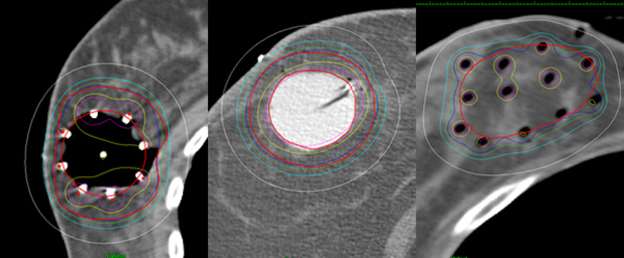

This is in contrast to these examples of standard whole breast radiation where the entire breast is considered the target.

A cartoon depiction of the tube and button implant showing the entrance and exit sites of the hollow tubes.

This is a cartoon example of a SAVI applicator sitting inside of a lumpectomy cavity and showing that a turn-key is used to expand the struts of the applicator so that it fits snug along the edges of the cavity.